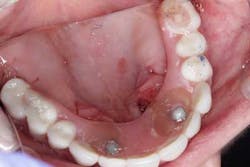

After a complete assessment, it was apparent that Sara’s options were limited with her existing dentition. The caries present were large and apple-cored around the teeth, making the long-term restorative prognosis questionable or guarded at best (figures 2-5). Several key teeth for partial abutments were either missing or grossly carious.

Surgery commenced. Implants on the lower arch were placed first (figures 7 and 8) and then we switched to the maxillary. The teeth were removed (figures 9 and 10) and the ridge was evened out (figures 11-13). The implants were aligned with the denture (figure 14) and then placed accordingly (figures 15-17). Healing caps were put on, and we were ready to start the restorative phase (figures 18-19).